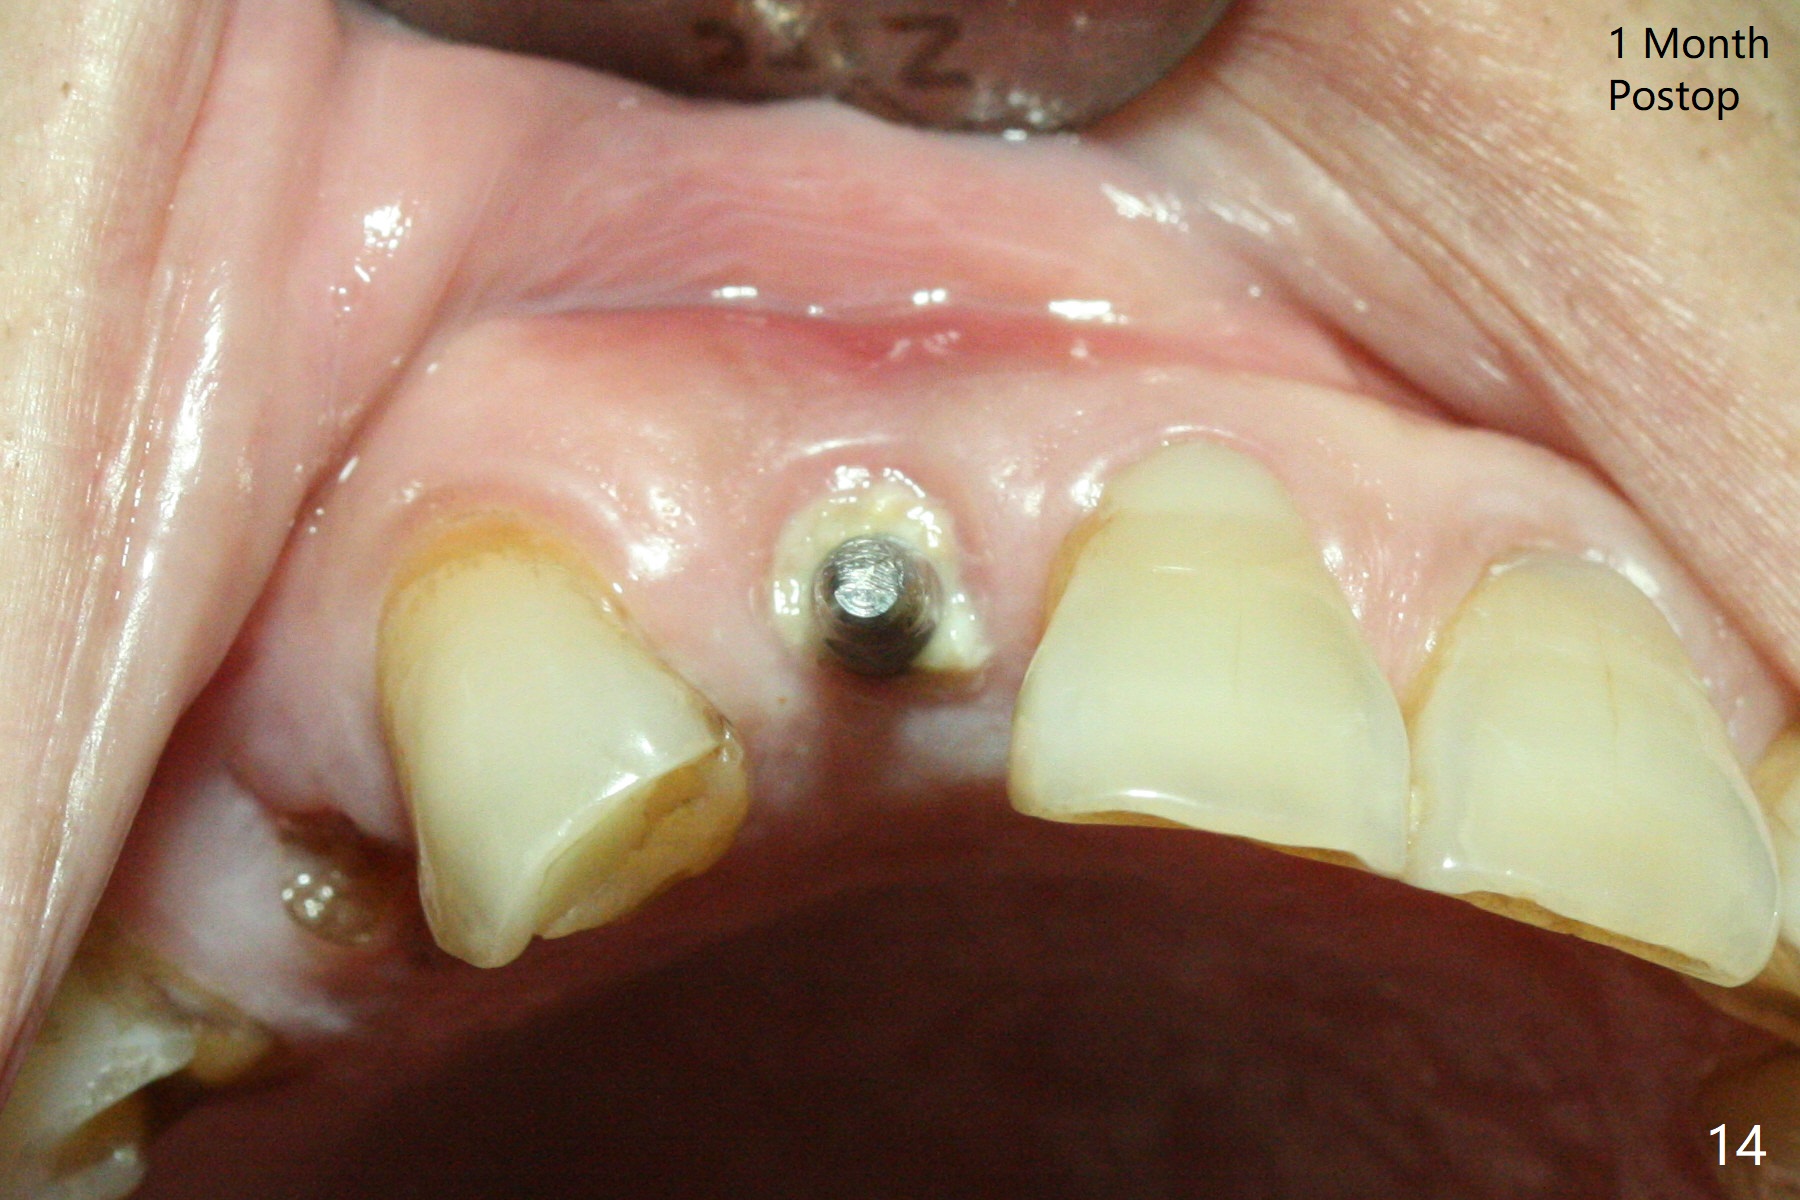

An apical abscess is present when the patient returns for immediate implant at #7 (Fig.1 *); a 2nd challenge is deep bite. After smooth extraction, the apical buccal plate is found to be perforated. Following debridement, a piece of gauze is placed in the apical defect for hemostasis, while osteotomy is initiated palatal (Fig.2). The apical defect seems to be extensive (Fig.3 yellow dashed line). A new trajectory is intended (red arrow) without much success. Before implant placement, bone graft is placed in the apical defect defect area, while a drill (Fig.4 D) is inserted in the finished osteotomy (Fig.5 O). In spite of seemingly large apical defect, the buccal crest bone exists (Fig.4 x). A 3x14(2) mm 1-piece implant is placed with stability; the first round of bone graft is apparently around the apical portion of the implant (Fig.6 *). The coronal end of the implant has to be adjusted several times buccopalatally to accommodate the deep bite. A 2nd round of bone graft following an immediate provisional closes the coronal space of the socket (Fig.7 *). CT will be taken to show the bone graft to repair the buccal plate defect when the patient returns for postop follow-up. In fact the defect is minimal in CT a month ago. The fistula does not disappear 1 week postop, but it is non tender (Fig.8). The patient complains of asymptomatic swelling in the right nostril. CT shows that the large buccal perforation is repaired with large amount of bone graft (Fig.9,10 *). It would be nicer to place the implant slightly more buccal apically (Fig.11 red lines; Fig.12 (preop design)). The buccoapical fistula disappears nearly 1 month postop (Fig.13). The apparently "lifeless" bone graft seems to be harmonious with the surrounding tissue (Fig.14). The periimplant gap reopens with implant mobility nearly 4 months postop (Fig.15), which is related to micro-movement associated with the immediate provisional. The latter is removed. A larger 2-piece implant will be placed in a 2-staged manner if needed (Fig.16). In fact the 3x14 mm straight 1-piece implant (Fig.17) has no mobility when it is retightened, but the trajectory remains buccal. Incision shows that there is no implant thread exposure. A 3x14 mm 15 degree angled 1-piece dummy implant is able to establish the correct trajectory, but there is no occlusal clearance (Fig.18). Micromovement during osteointegration may recreate loosening. Finally using Lindamann bur, the osteotomy is changed so that a 3.5x13 mm 2-piece implant does not need an angled abutment to establish occlusion (Fig.19). There is one palatal thread exposure. Allograft is placed circumferentially, followed by Human Amnion-Chorion Allograft and Collagen Plug. The wound does not heal 8 days postop (Fig.20), as related to the age (79 years old)? The wound appears to heal with a membrane on the surface (Amnion-Chorion one?) 3 weeks postop (Fig.21). The ridge looks wide 3.5 months postop (Fig.22,23). A 4.5x5.5(3) mm appears to be seated incompletely with a gap between the abutment and the implant (Fig.24<). A provisional is fabricated after heavy palatal reduction. Two months later, the provisional fractures. After repositioning the abutment with complete seating and torque (Fig.25), impression is taken. Although the buccal plate is concave, the gingiva remains healthy 10 months post cementation (Fig.26,27).